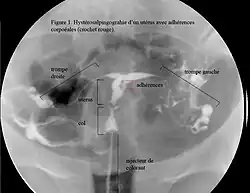

Une aménorrhée avec un historique de curetage pratiqué après une grossesse est typique. L’hystéroscopie est la méthode idéale pour poser un diagnostic[8]. Les images obtenues par hystérosonographies ou par hystérosalpingographie révèlent l’étendue des cicatrices et adhérences (synéchies). L’échographie seule n’est pas une méthode fiable pour le diagnostic du syndrome d’Asherman. Les analyses hormonales montrent souvent des taux normaux compatibles avec les fonctions reproductrices, ce qui élimine la possibilité des troubles menstruels dus aux dérèglements hormonaux.